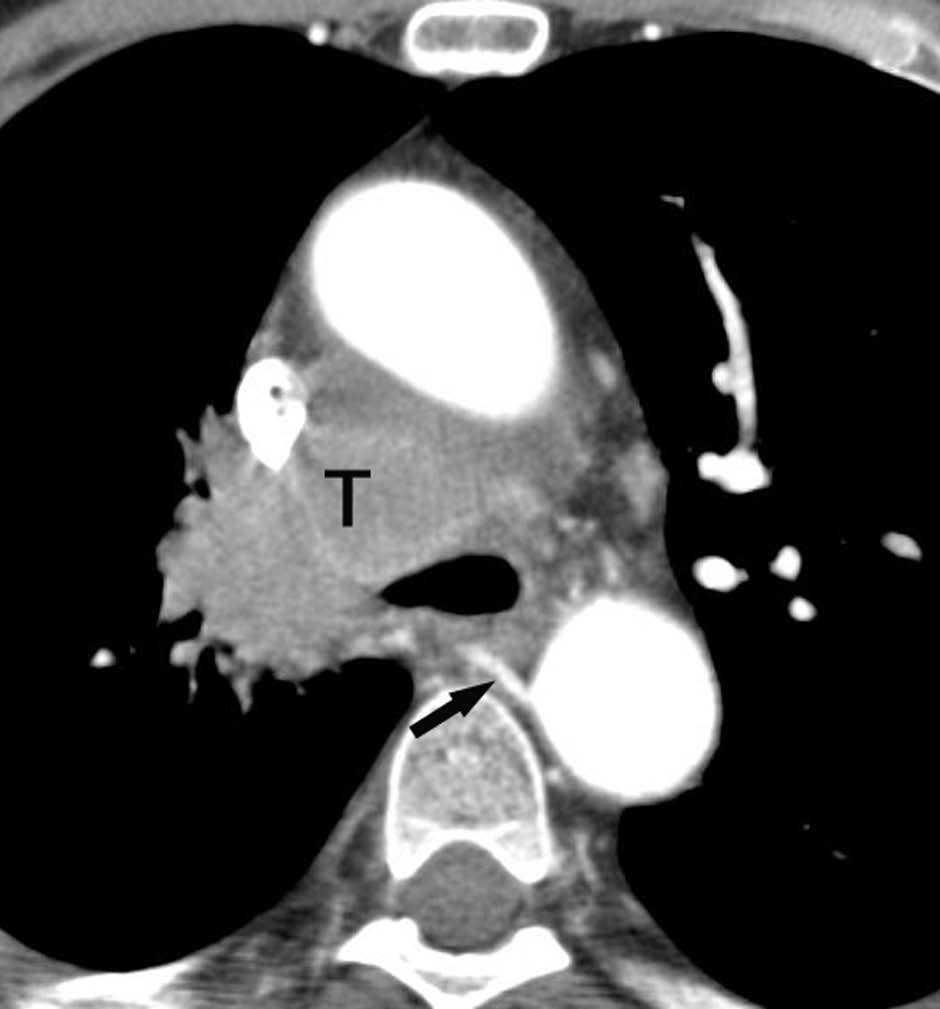

Fig. 4.--Invasión vascular. Tomografía computarizada (TC) torácica con contraste. Corte axial (A) y reconstrucción coronal oblicua (B). Invasión tumoral por continuidad de la vena pulmonar inferior (flecha).